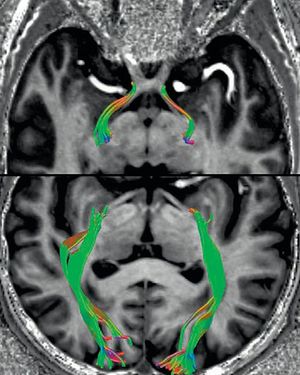

Selective tractography of the optic tract.

Selective tractography of the optic tract and the optic radiation using high resolution DTI fused with axial MPRAGE. Image dataset was acquired at 7 Tesla, Siemens Magnetom Terra.